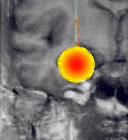

MR systems can also be used to measure the temperature within the brain during a laser-induced interstitial thermo therapy. As the coagulation process is difficult to predict due to irregularities in tissues and thermo convection, an interventional MR system can be used to control whether the therapy proceeds as planned or whether the plan has to be modified. This asks for a fusion of current MR images with respective images of the therapy planning.

Figure 6:

left: texture-based rendering of a 3D-CT-volume in real-time

right: shadows added to improve depth perception